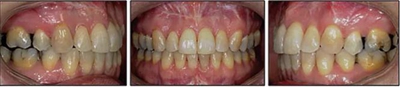

患者曾行正畸治療,現覺笑容不美觀前來就診?;颊哒嬗^及側貌示下頜發(fā)育不足,偏高角,唇閉合不全。上下頜中線齊。覆合、覆蓋4毫米。磨牙關系及尖牙關系II類。上頜擁擠度4mm,下頜擁擠度6mm。4顆第一前磨牙在第一次正畸治療時已拔除。上下牙弓呈尖圓型,牙弓狹窄。

治療結果:

患者側貌改善,下唇唇肌緊張消失,上下唇可自然閉合。磨牙及尖牙關系糾正至I類,覆合覆蓋正常。上下頜弓型糾正至卵圓形,牙弓寬度增加。頭影測量分析示SNA角81.8°,ANB角3°。頭影測量重疊圖示下頜骨向后旋轉,垂直面高度略有增加。